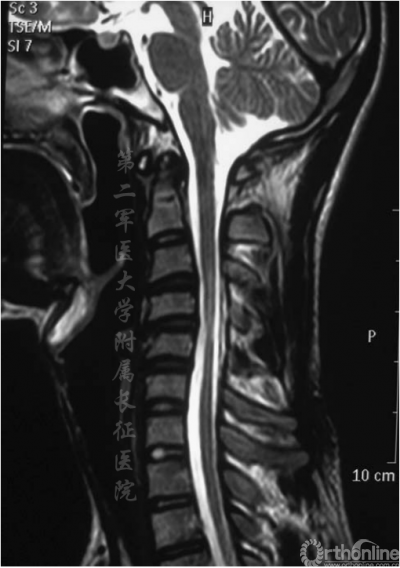

图1.术前侧位MRI显示脊柱后凸,支点在C4-C5水平,颈脊髓明显萎缩

颈椎中立位MRI可见颈椎后凸在C4-C5或C5-C6处具有顶点(图1),且脊髓出现轻度萎缩。屈颈位MRI可见硬膜外高信号影及硬膜囊后壁前移(图2)。头颅MRI未显示异常。根据MRI将患者诊断为平山病伴颈椎后凸畸形。入院三天后,患者在全麻下接受颈前路椎间盘切除术并在C3-C7水平融合以重建颈椎序列和脊柱前凸(图3)。